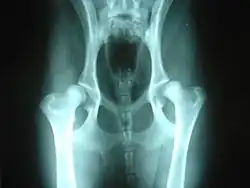

Hip dysplasia is diagnosed with radiographs of the pelvis. It is also common to X-ray the spine and legs, as well as the hips, since soft tissues can be affected by the extra strain of a dysplastic hip, or there may be other undetected factors such as neurological issues (e.g. nerve damage) involved.